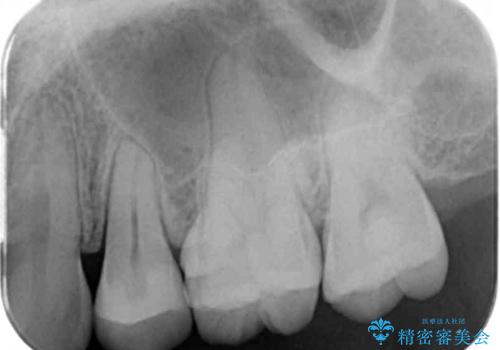

銀の詰め物を白くしたい セラミックインレーでの治療

- 銀歯が気になるためやり替えたいとのことで来院されました。

セラミックインレーで治療を行いました。

- 左上5 セラミックインレー 77,000円費用は治療当時の料金となります